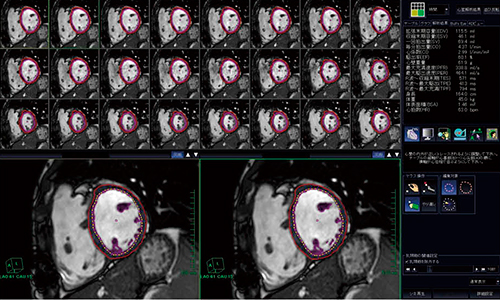

1.心機能解析

心室に対し短軸で撮像したcine画像より,左右の心室容量や拍出量,駆出率などの心室機能解析を行う。左心室機能解析に関しては,以前より搭載されているソフトウェア“MRI心駆出率解析”を使用して行っている(図1)。

CHD MRI検査で重要な右心室機能解析には,今回新しく導入されたソフトウェア“MRI右心室解析”を使用している。このソフトウェアの特徴は,1つの画像でROIを設定すると,「全フェーズの同じ位置のスライスにROI作成」のボタンが表示されることである。当院では1スライス30phaseでcine撮像をしているので,ワンクリックで残りの29画像すべてのROIをほぼ修正なしで自動表示することができ,ROI設定の労力軽減に有用な機能となっている。さらに,必要なスライスすべてのROI設定と同時に解析結果も表示されるため,結果確認も容易に行うことができる。このソフトウェアの使用により,解析時間の短縮・解析結果の精度向上と,心臓カテーテル検査では困難な心室容積の測定に威力を発揮している(図2)。

図1 “MRI心駆出率解析”による左心室機能解析

図2 “MRI右心室解析”による右心室機能解析

「全フェーズの同じ位置のスライスにROI作成」(○)をクリックすることにより,他の画像にもROIが自動表示される。